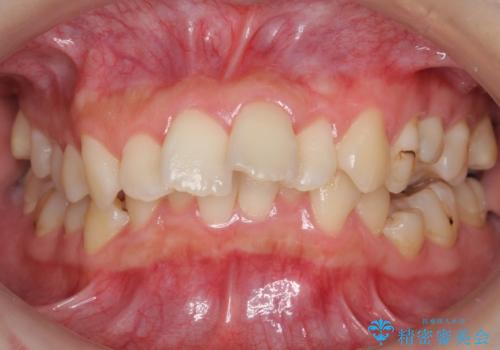

【難症例】歯並びが悪く、虫歯の治療ができない 矯正治療からスタート

左上の小臼歯が込み合っており、虫歯治療が厳しい状態でした。

矯正治療をおすすめし、ちょうど虫歯がひどい歯は抜歯して前歯を下げました。